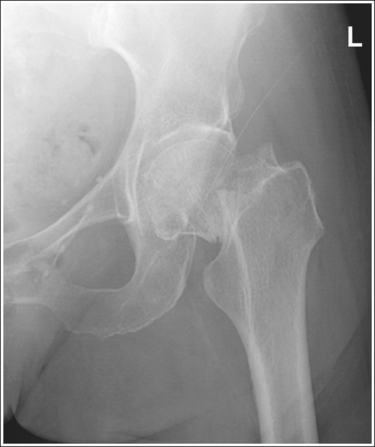

• Detecting pelvis rotation. Rotation on an AP hip projection is initially detected by evaluating the relationship of the ischial spine and the pelvic brim, the alignment of the sacrum and coccyx with the symphysis pubis, and the degree of obturator foramen demonstration. If the patient was rotated toward the affected hip, the ischial spine is demonstrated without pelvic brim superimposition, the sacrum and coccyx are not aligned with the symphysis pubis but are rotated away from the affected hip, and the obturator foramen is narrowed (see Image 1). If the patient has been rotated away from the affected hip, the ischial spine is not aligned with the pelvic brim but is demonstrated closer to the acetabulum, the sacrum and coccyx are not aligned with the symphysis pubis, but are rotated toward the affected hip, and the obturator foramen is widened (see Image 2).

IMAGE 1

The ischial spine is demonstrated without pelvic brim superimposition, the sacrum and coccyx are not aligned with the symphysis pubis but are rotated away from the affected hip, and the obturator foramen is narrowed. The patient was rotated toward the affected hip. The femoral neck is foreshortened, and the lesser trochanter is demonstrated in profile. The patient's leg was externally rotated.

Rotate the patient away from the affected hip until the ASISs are positioned at equal distances from the imaging table. Internally rotate the patient's leg until the foot is angled 15 to 20 degrees from vertical and the femoral epicondyles are positioned parallel with the imaging table, as shown in Figure 7-4.